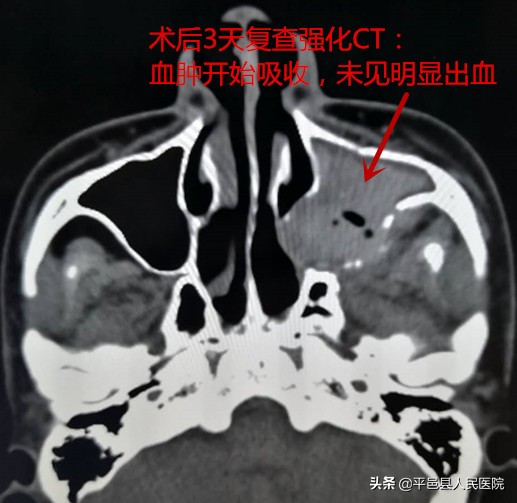

放射介入科行左侧颈外动脉造影发现患者出血原因为外伤后致左侧上牙槽后动脉破裂所致,紧急栓塞该血管,术中血管造影显示出血停止。术后患者未再出现鼻出血,康复出院。